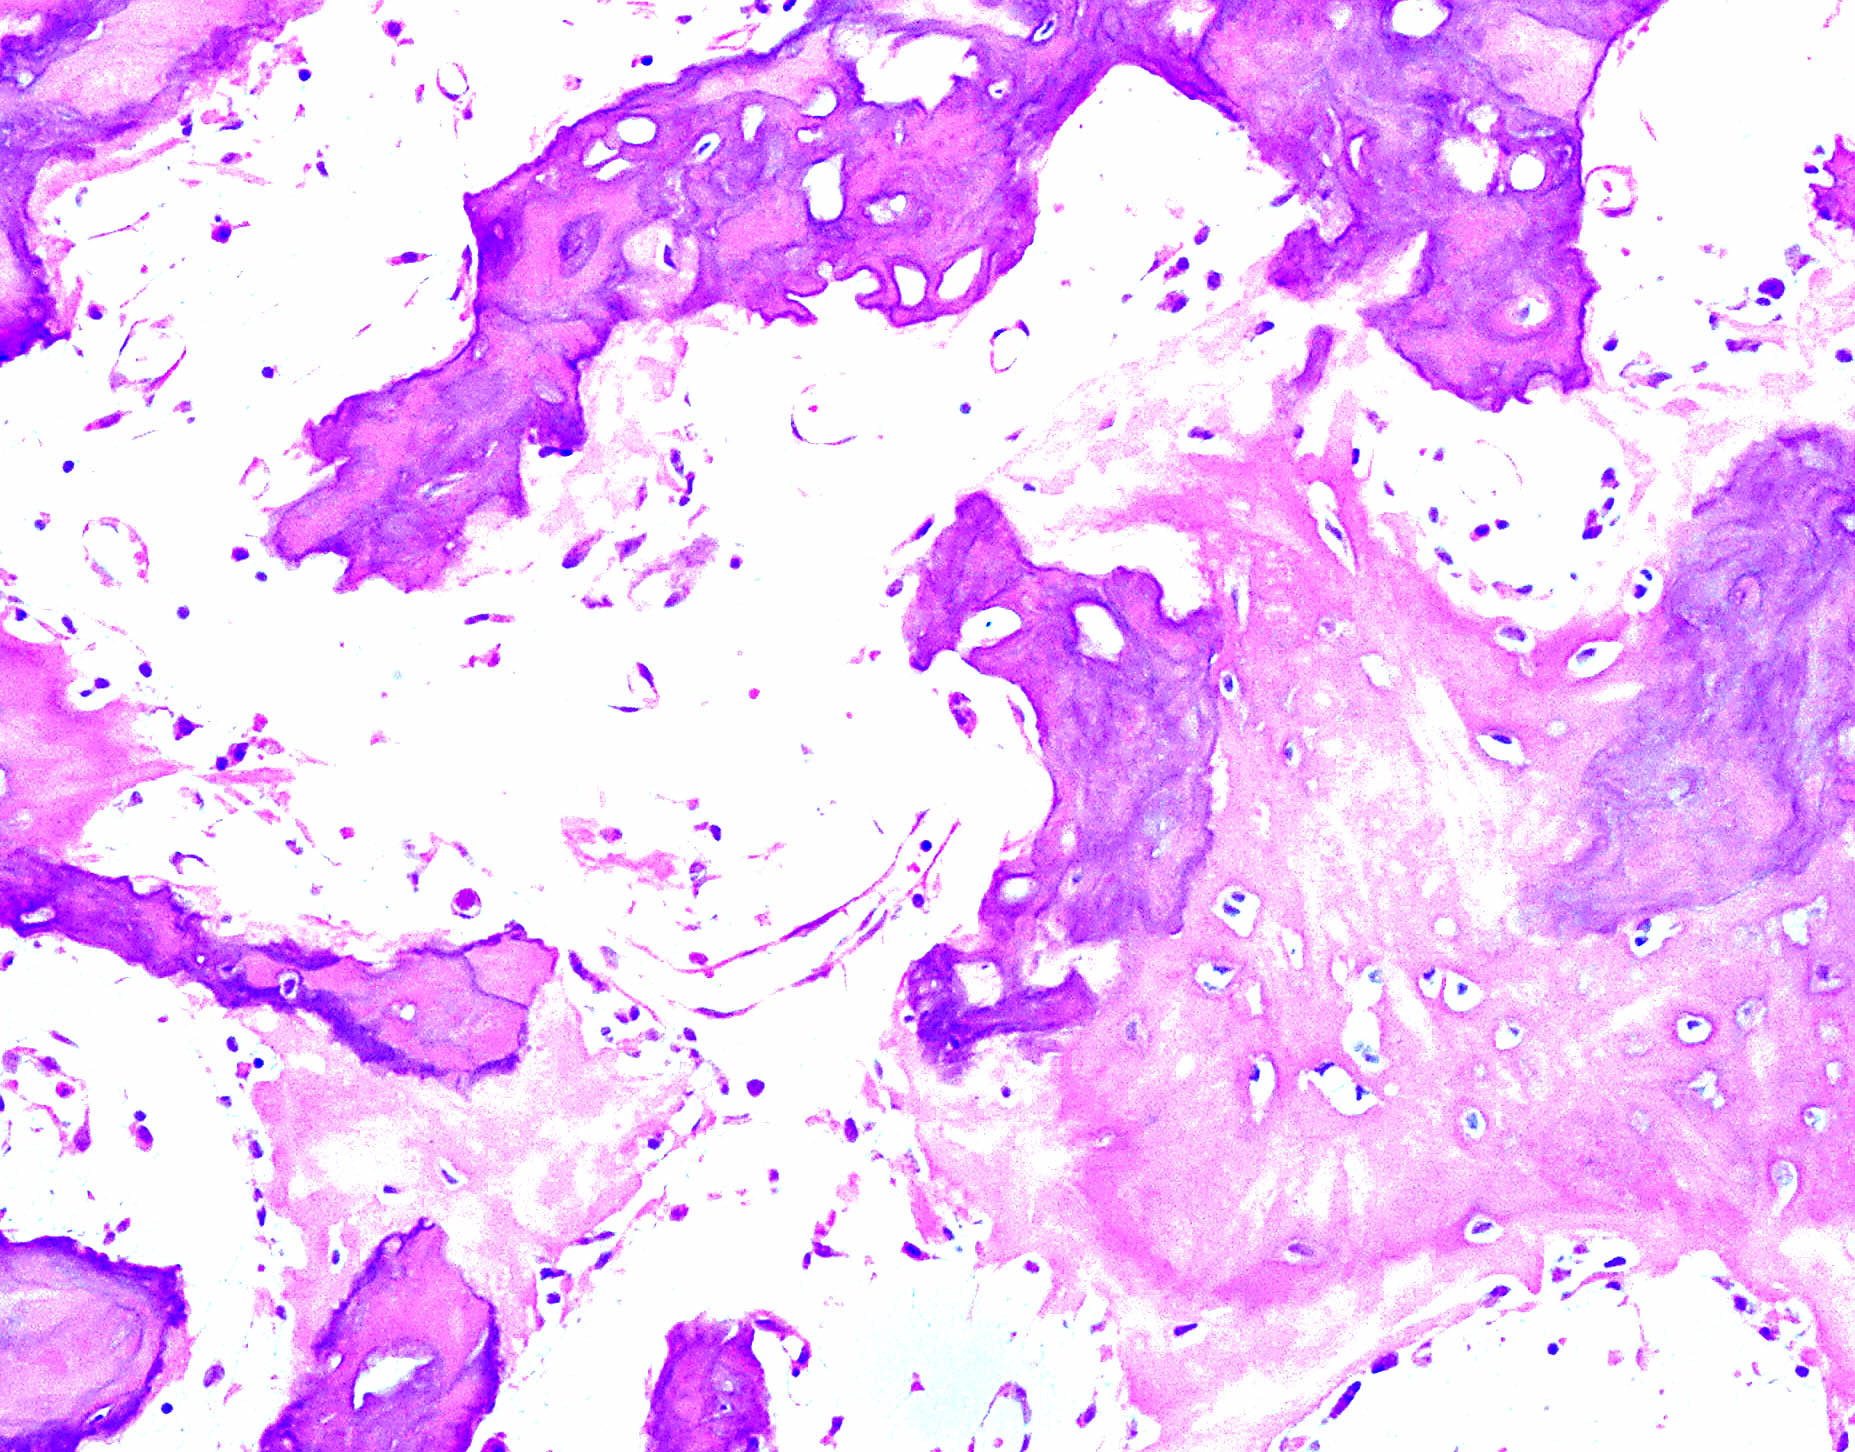

Paget's Disease Pathology Outlines . Underlying breast lesion is usually a. Paget disease's pathological process occurs in 4 stages. It begins with osteoclastic activity, followed by a hybrid osteoclastic/osteoblastic. Paget's disease of the breast is an uncommon manifestation of underlying breast cancer in postmenopausal female patients. Paget disease versus melanoma versus squamous cell carcinoma in situ. Paget's disease is an idiopathic condition of abnormal bone remodeling with normal bone being replaced through an active. Paget disease of bone most commonly presents with a pathologic fracture but can present as generic bone pain. Extramammary paget disease (empd) is defined as intraepidermal adenocarcinoma and may originate from the.